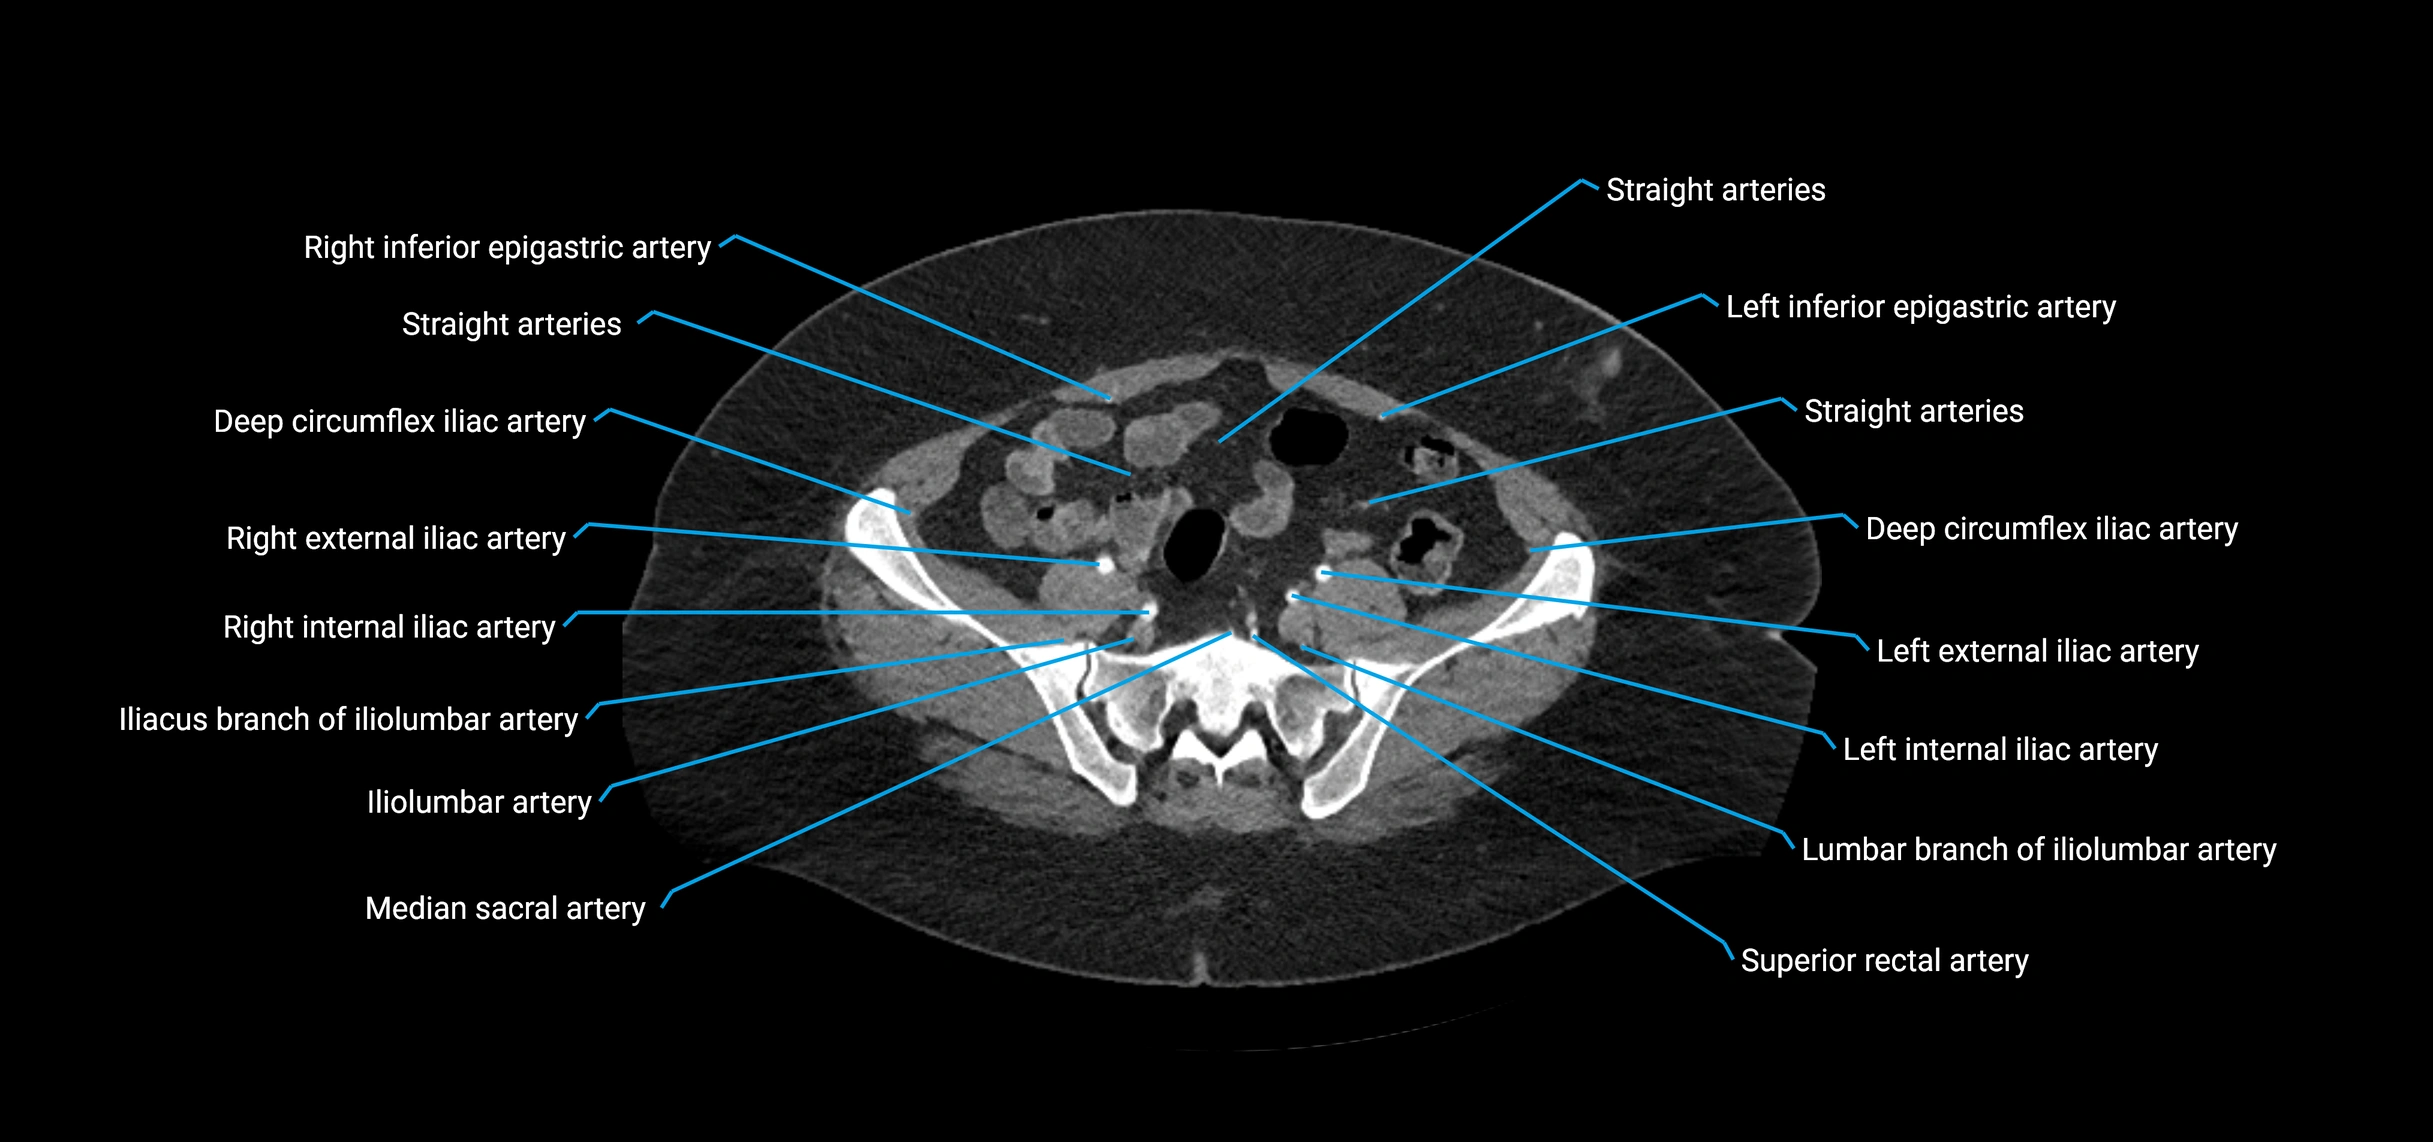

CT images

image

Contrast-enhanced CT (CTA):

• Gold standard for abdominal aortic imaging

• Provides excellent detail of lumen, wall, aneurysm, thrombus, and branch vessels

• Multiplanar and 3D reconstructions help in aneurysm measurement, stent graft planning, and dissection evaluation

• Detects acute rupture, traumatic injury, or occlusion with high sensitivity